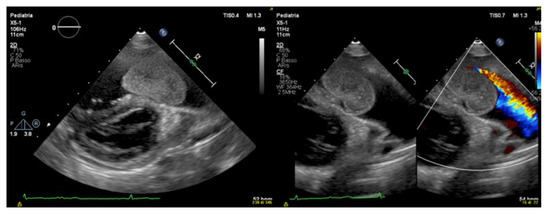

Echocardiogram identified a rounded and lobulated voluminous (3.5 × 4 cm) mass with clear margins and inhomogeneous content, adherent to the infundibular septum through a pedicle. The right ventricle outflow tract (RVOT) showed a severe obstruction with a maximum instantaneous systolic gradient of 80 mmHg, sparing the pulmonary valve (Figure 2 and Figure 3). The right atrium (Area 23.5 cm2) and ventricle (tele-diastolic area was 23 cm2 and tele-systolic 19 cm2) were dilated with a severe systolic dysfunction (Fractional Area Change of 18.6%).

Figure 2.

Color Doppler transthoracic echocardiography.

Transthoracic echocardiography shows the presence of a mobile intracardiac mass protruding into the right outflow, attached to the infundibular septum by a peduncle.